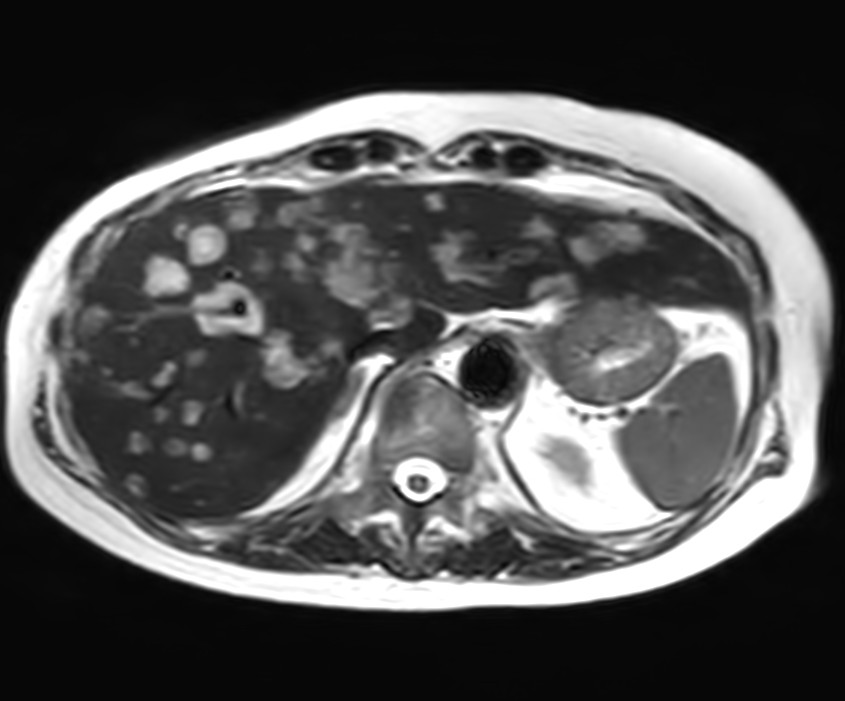

Liver metastasis with SmartSpeed Precise

Axial Heavy T2w SSh FatSat